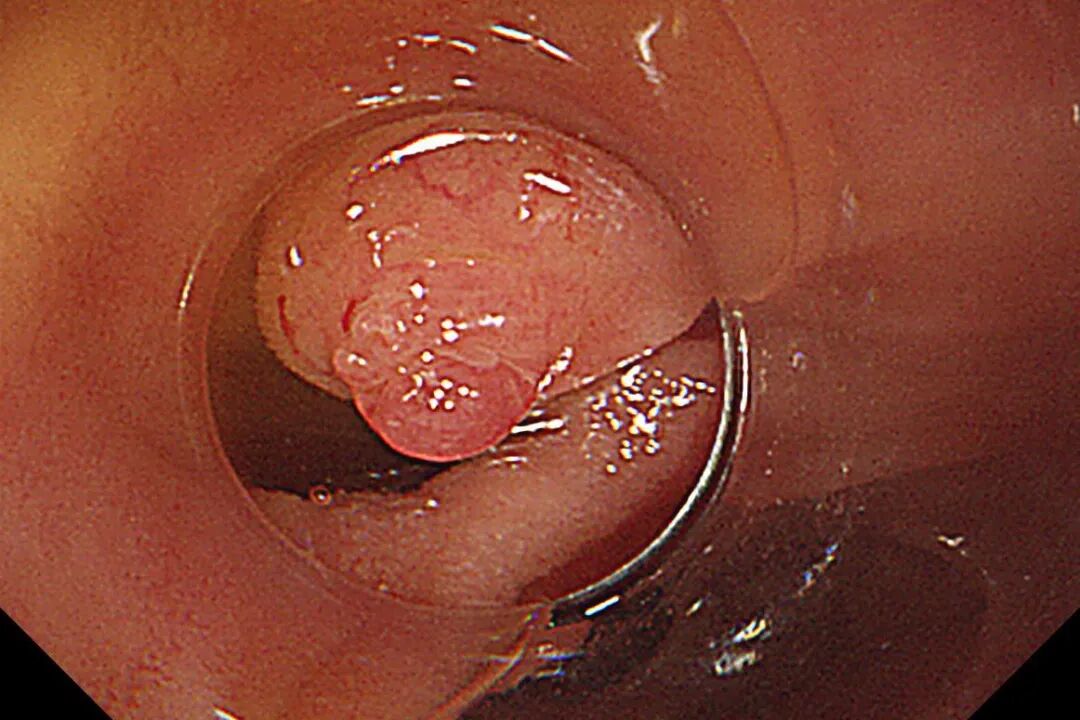

图片

术中-网篮取出结石

术中胃镜戴透明粘膜吸套进镜,可见胃、十二指肠、空肠呈B-II式术后改变,吻合口发红。经团队仔细查找,于输入袢找到十二指肠大乳头,插入三腔括约肌切开刀,并顺利将导丝送入胆总管。造影验证,可见胆总管明显扩张,直径最宽处约16mm,中段见一长条形结石影,约13x12mm。切开乳头后,扩张乳头括约肌及胆总管括约肌,用特制取石导管及取石网篮取出大量黄色块状结石及碎渣样结石。术后置入鼻胆引流管引流,顺利结束手术

术后造影-胆管通畅